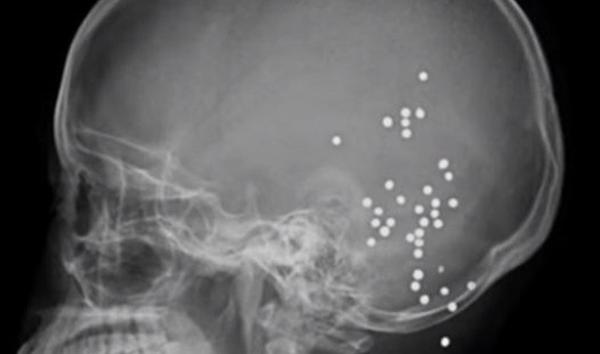

بالفيديو .. صينية تنجو من الموت رغم إصابتها بـ36 رصاصة في الرأس